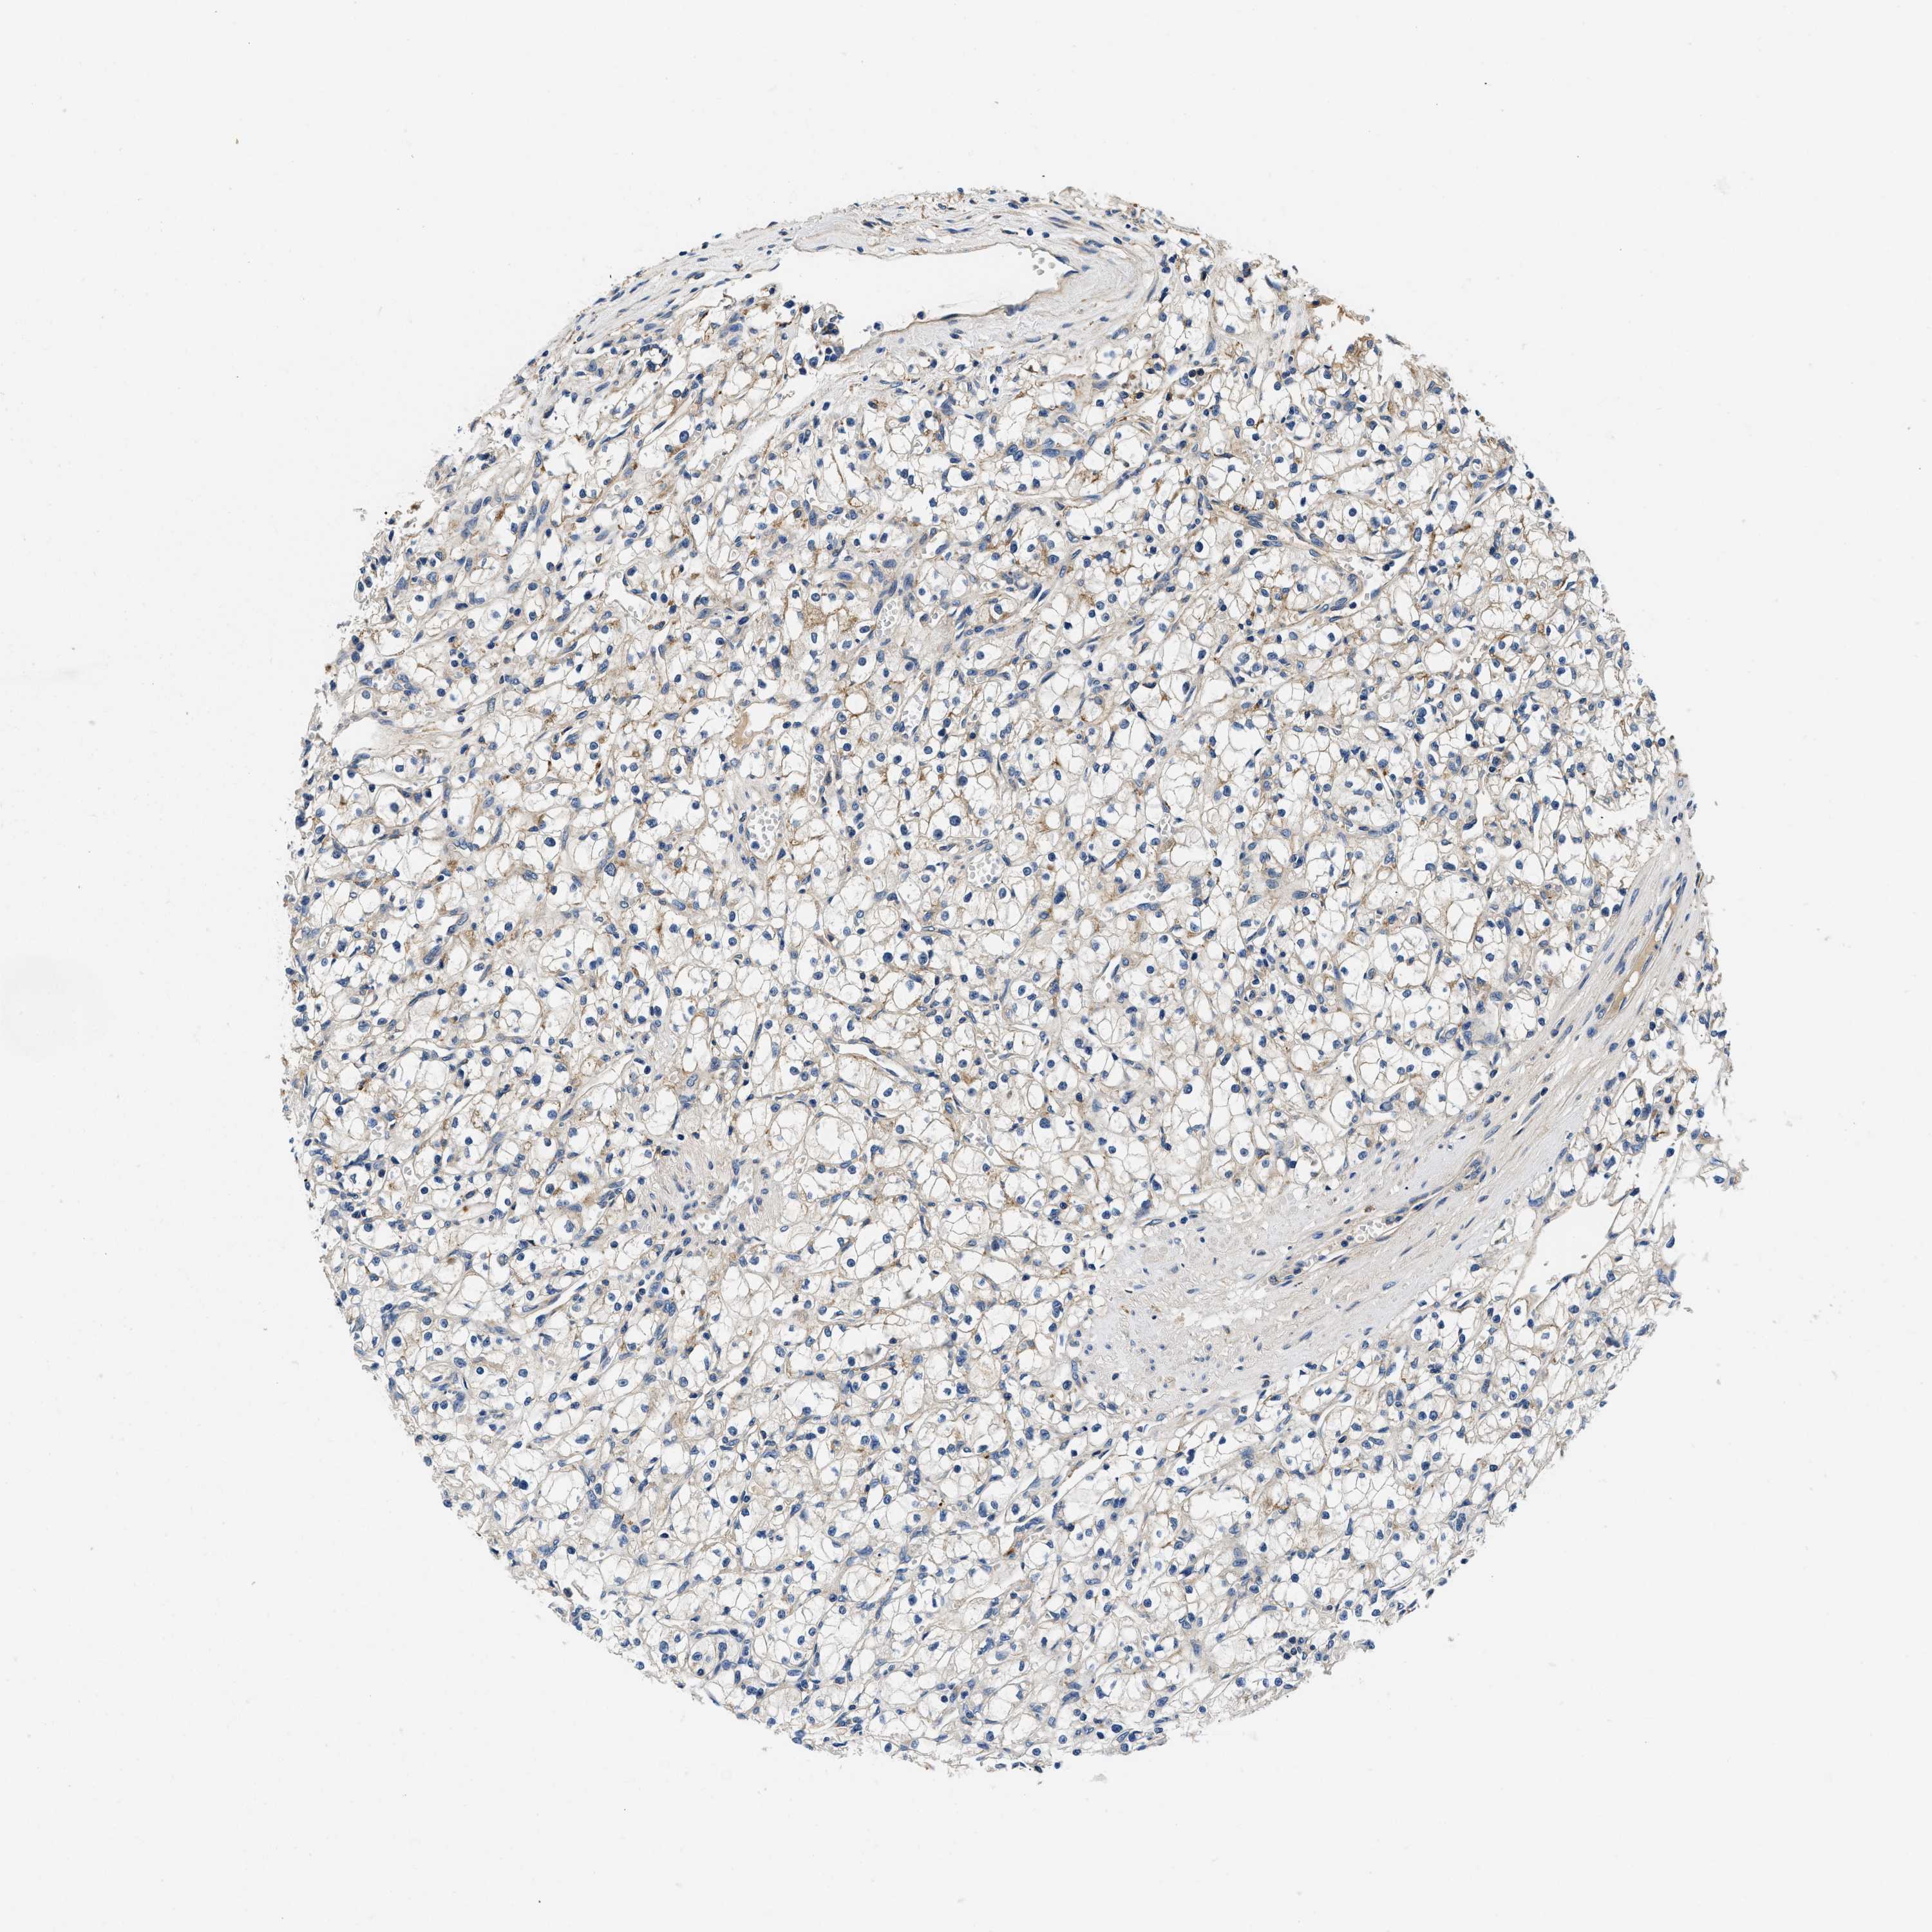

KIDNEY RENAL CLEAR CELL CARCINOMA (VALIDATION) - Interactive survival scatter ploti

ZFAND3 is not prognostic in Kidney Renal Clear Cell Carcinoma (validation)

: 52.03

Average pTPM 62.4

Number of samples 100